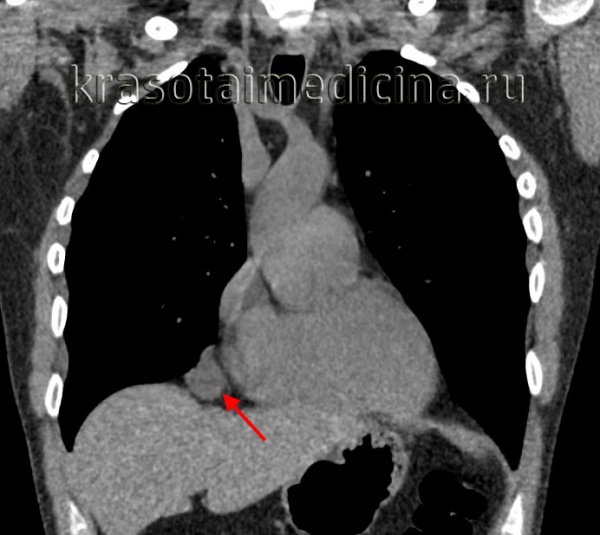

КТ органов грудной клетки — картина кистозного образования средостения слева. Небольшой объем жидкости в плевральной полости слева и в перикарде ( рис. 2 ).

Рис. 2. Компьютерная томограмма грудной клетки девочки Т., 9 лет. Иллюстрация М.Ю. Петрова, заведующего отделением, врача-рентгенолога ГАУЗ АО «Амурская областная детская клиническая больница»